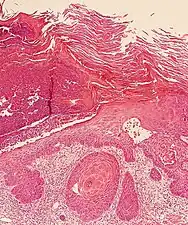

In invasive cSCC, tumor cells infiltrate through the basement membrane. The infiltrate can be somewhat difficult to detect in the early stages of invasion: however, additional indicators such as full thickness epidermal atypia and the involvement of hair follicles can be used to facilitate the diagnosis. Later stages of invasion are characterized by the formation of nests of atypical tumor cells in the dermis, often with a corresponding inflammatory infiltrate.[12]

Superficially invasive cutaneous squamous-cell carcinoma. These lesions often do not show the marked pleomorphism and atypical nuclei of cSCC in situ, but manifest early keratinocyte invasion of the dermis.[12]

Invasive nests with characteristic large celled centers. Ulceration (at left) is common in invasive cSCC.